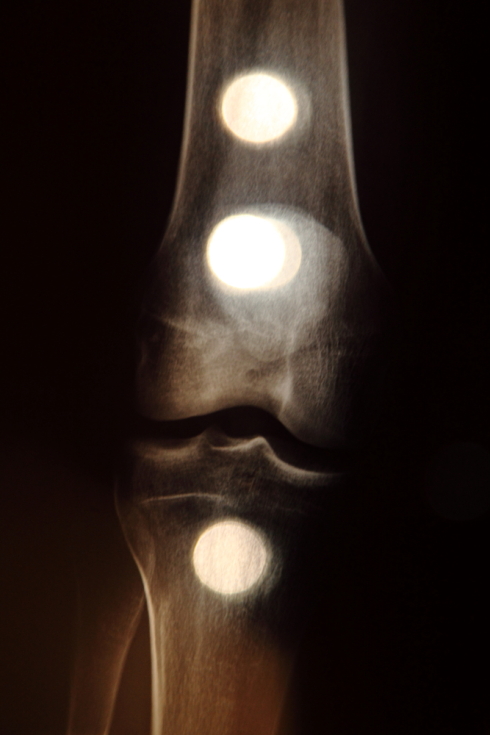

Photo works

Dreams